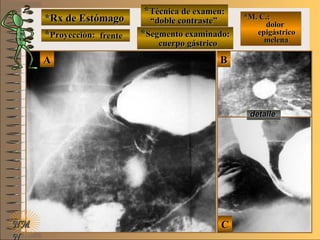

*Rx de Estómago*Rx de Estómago

**Proyección:Proyección:

**Técnica de examen:Técnica de examen:

**Segmento examinado:Segmento examinado:

*M. C.:*M. C.:

epigastralgiaepigastralgia

NMNM

detalledetalle

frentefrente

““doble contraste”doble contraste”

cuerpo gástricocuerpo gástrico

A-A-El examen es normal o patológico?El examen es normal o patológico?

Examen patológico de estómago con técnicaExamen patológico de estómago con técnica

de doble contraste en proyección de frentede doble contraste en proyección de frente

E-E-Puede describir la o las imágenes patológicas?Puede describir la o las imágenes patológicas?

Se identifica una pequeñaSe identifica una pequeña imagen deprimidaimagen deprimida

UNTUNT en cara posterior de cuerpo gástrico conen cara posterior de cuerpo gástrico con

convergencia radiada de pliegues, que corres-convergencia radiada de pliegues, que corres-

ponde a ulcera péptica en actividad (verponde a ulcera péptica en actividad (ver ciclociclo

de Sakitade Sakita UNTUNT ))